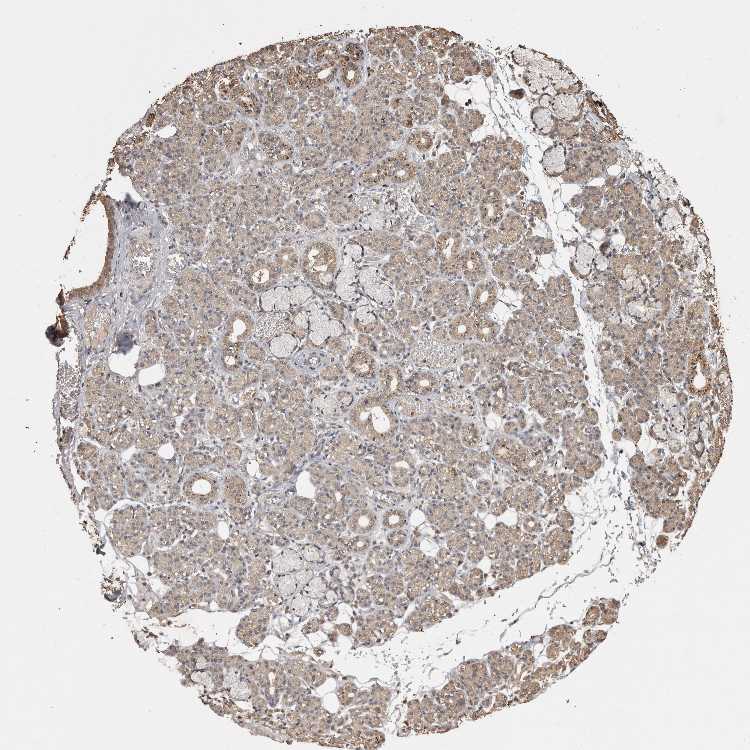

SALIVARY GLAND - Antibody stainingi

Antibody staining in the annotated cell types in the current human tissue is reported as not detected, low, medium, or high, based on conventional immunohistochemistry profiling in selected tissues. This score is based on the combination of the staining intensity and fraction of stained cells.

Each image is clickable and will lead to virtual microscopy that enables deeper exploration of all samples and also displays staining intensity scores, fraction scores and subcellular localization as well as patient and tissue information for each sample.

Antibody HPA020884Antibody CAB025510

Glandular cells Not detectedMedium